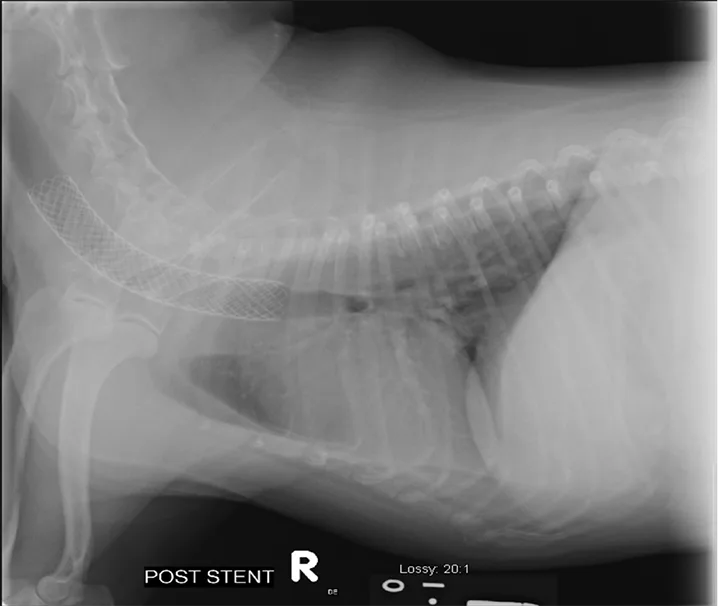

In patients with an ongoing cough that cannot be controlled with medical management, evaluation for pulmonary hypertension via echocardiography should be considered.2 Lower airway disease can contribute to significant pulmonary hypertension, and treatment of pulmonary hypertension with sildenafil (starting dosage, 0.5-1 mg/kg PO every 8 hours) can improve cough.2 However, placement of an intraluminal tracheal stent can be considered when a patient fails to respond to aggressive and appropriate medical management and the tracheal collapse is severe enough to prevent effective ventilation.1-4,11 During placement of a tracheal stent, fluoroscopy is used to deploy the stent across the affected portion, or entire length of the trachea, to physically hold the trachea open. This procedure is noninvasive and can be lifesaving in dogs with severe tracheal collapse (Figure 2). In dogs with tracheal collapse and concurrent complicating factors (eg, severe lower airway disease) that cannot be appropriately removed or managed, placement of a tracheal stent may not be beneficial to achieve significant improvement of clinical signs.2,4

Stent placement across a focal severe thoracic inlet tracheal collapse